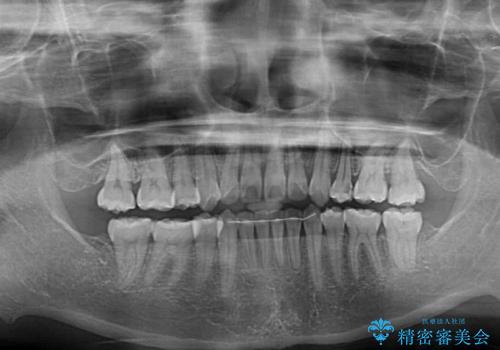

- 前歯のデコボコや口元の突出感、口の閉じにくさを気にして来院された患者様です。

上下左右第一小臼歯4本を抜歯し、ワイヤー装置にてデコボコを解消しながら口元を引っ込めるよう矯正治療を行うこととしました。

抜歯スペースを閉じている過程で、左側の上下犬歯が引っかかってしまい、進捗が停滞しましたが、当初予定の2年~2年半の間で無事に治療を終えることができました。